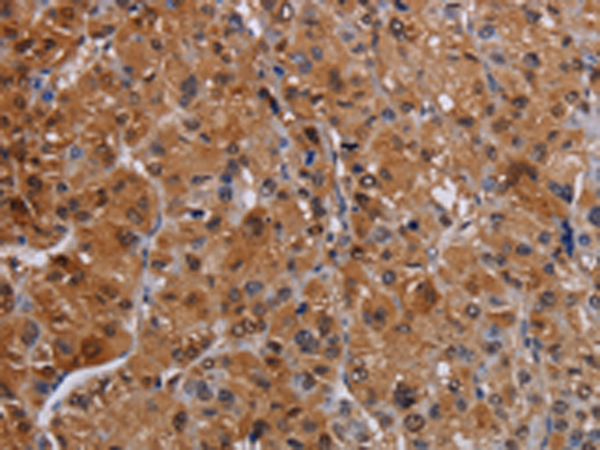

分类: 科研抗体货号: P08480别名: PINCH; PINCH1; PINCH-1应用: WB,IHC反应种属: Human, Mouse